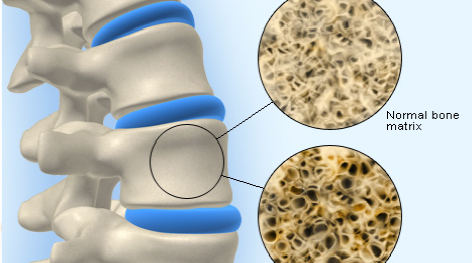

Es una enfermedad caracterizada por la disminución de la densidad de la masa ósea por un defecto en la absorción del calcio; ocasionando una alteración en la calidad del tejido oseo lo que hace que los huesos sean más frágiles incrementando con ello el riesgo de fracturas, especialmente en la cadera, antebrazo, muñeca y columna vertebral.